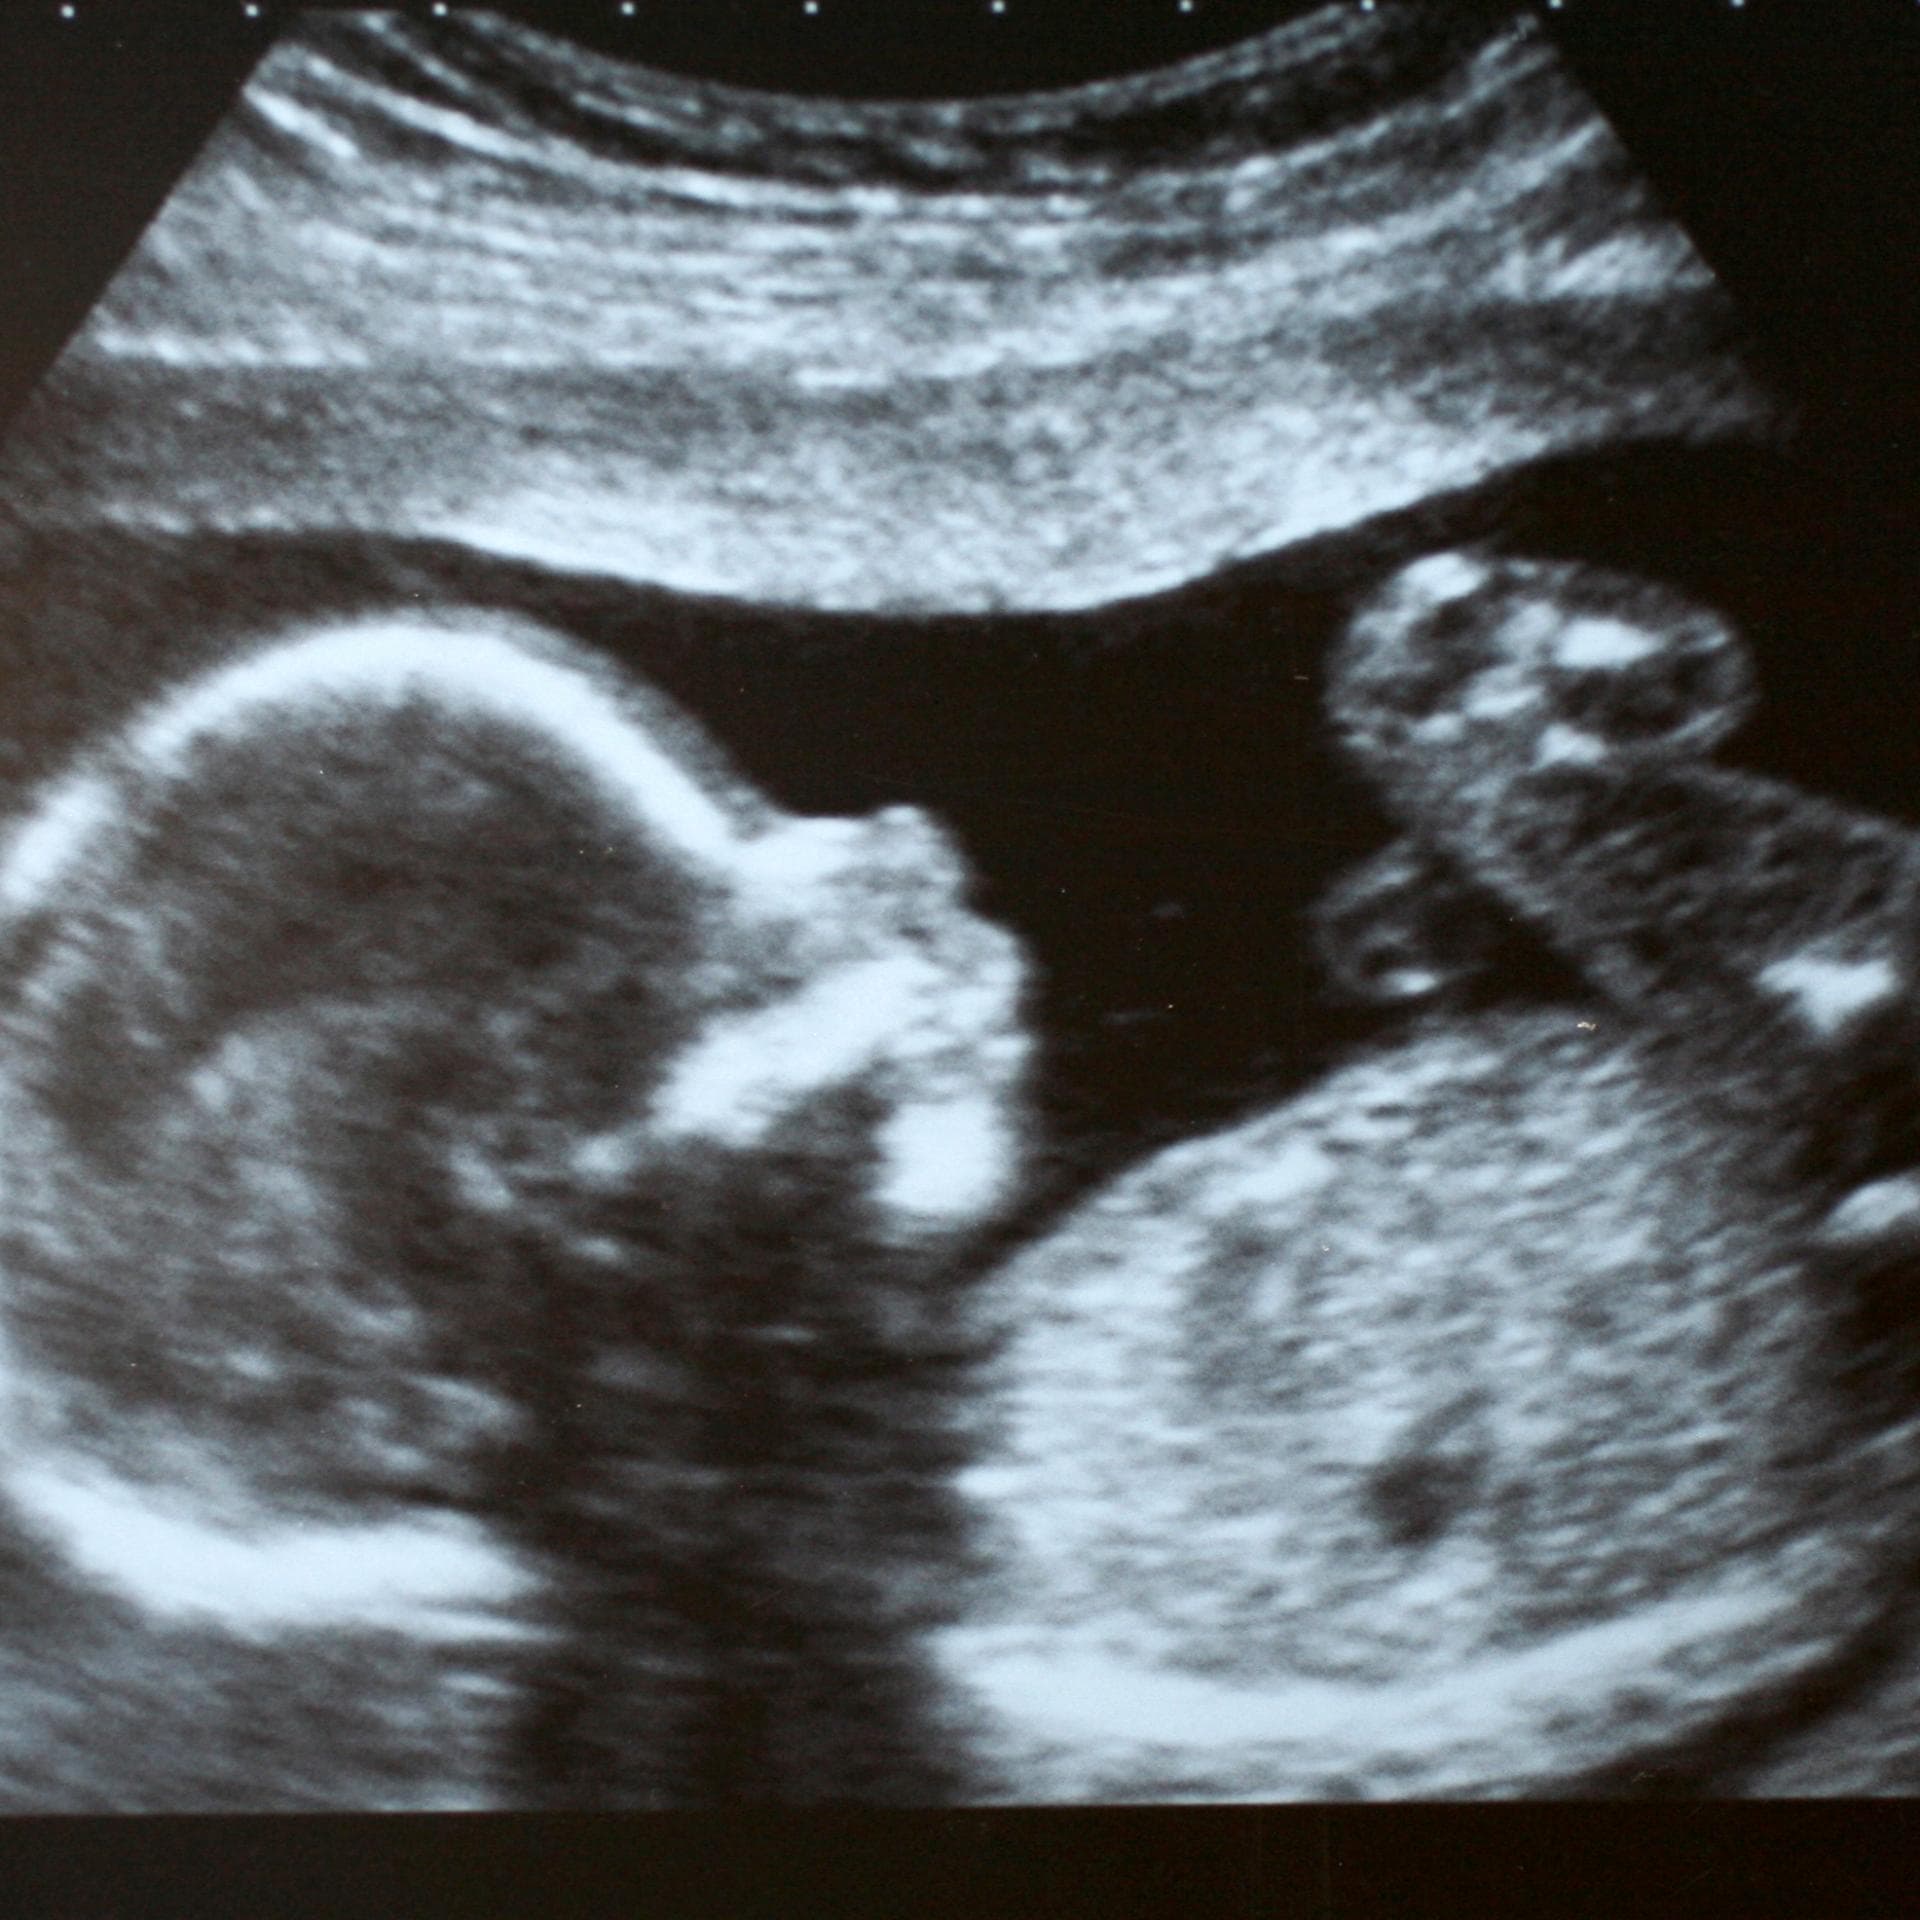

Eineiige Zwillinge sollten im ersten Schwangerschaftsdrittel mit Hilfe einer Ultraschall-Untersuchung beurteilt werden. "Ein Gynäkologe kann am besten zwischen der achten und der zwölften Schwangerschaftswoche abschätzen, ob es sich um eineiige oder zweieiige Zwillinge handelt", erklärt Dr. Klaus König, zweiter Vorsitzender des Berufsverbandes der Frauenärzte (BVF).

"In diesem Zeitfenster kann man erkennen, ob sich die Babys in zwei getrennten oder in einer Embryonalhülle (Chorion) entwickeln. Weist die Gebärmutter zwei Embryonalhüllen auf, handelt es sich in der Regel um zweieiige Zwillinge. Sind beide von einer gemeinsamen Hülle umgeben, sind es höchstwahrscheinlich eineiige Geschwister. Werden beide von einer gemeinsamen Plazenta versorgt, sind sie eindeutig eineiig."

Nach der 16. Schwangerschaftswoche wird es praktisch unmöglich, eine Zwillingsschwangerschaft zu beurteilen, denn ab diesem Zeitpunkt liegt die Embryonalhülle zu nahe an der inneren Gebärmutterwand und ist dann nicht mehr hinreichend einsehbar. Die Diagnose, ob eineiige oder zweieiige Zwillinge vorliegen, kann sehr bedeutend für den Verlauf der Schwangerschaft sein, denn eineiige Zwillinge müssen besonders gut überwacht werden.